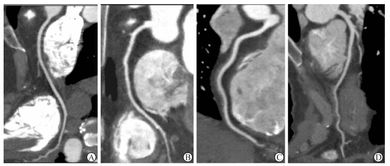

在X線球管連續(xù)旋轉(zhuǎn)和曝光的同時(shí),掃描床也連續(xù)勻速推進(jìn),從而獲得感興趣區(qū)的容積數(shù)據(jù)。這些容積數(shù)據(jù)不僅可以轉(zhuǎn)變?yōu)榕c常規(guī)機(jī)相同的橫斷面圖像,而且還能進(jìn)行多軸面的三維重建。

螺旋CT掃描診斷腰椎間盤突出癥的準(zhǔn)確率為90%-99%,其具有以下幾個(gè)特點(diǎn):①安全基本無損害,診斷的陽性符合率高;②可用于鑒別椎間盤膨出和椎間盤突出,并可識別其突出的部位和突出的大小,如中央型或側(cè)后型突出,還能顯示出硬膜囊和神經(jīng)根受壓的形態(tài)變化;③有助于避免L5-S1平面硬膜外間隙增大引起的假陽性;④適用于造影劑過敏,造影失敗或不愿接受造影檢査的患者;⑤可以在觀察椎間盤的同時(shí),顯示黃韌帶、后縱靭帶側(cè)隱窩、椎管和關(guān)節(jié)突關(guān)節(jié)的變化。 (3)增強(qiáng)掃描:靜脈注射造影劑后,進(jìn)行掃描的方法稱增強(qiáng)掃描或稱強(qiáng)化掃描。